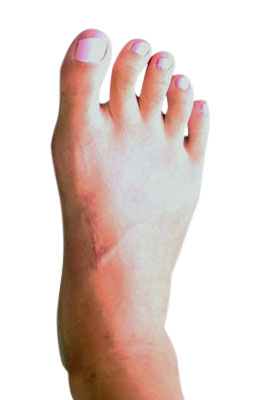

Before

Lapidus Forever Bunionectomy™ Before image

After

Lapidus Forever Bunionectomy™ after image

Lapidus Forever Bunionectomy™

Whitney, a 47-year-old businesswoman who could not fit into her dress shoes because of her bunion and terrible calluses caused by it. We performed a Lapidus Forever Bunionectomy™ on her big toes and she was able to bear weight on her foot 2 weeks after surgery and was back in her heels at 8 weeks post-surgery with no pain and now an amazing looking foot. After image was taken 12 weeks post-op.